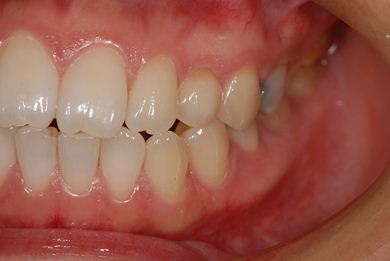

治療前

• 治療前